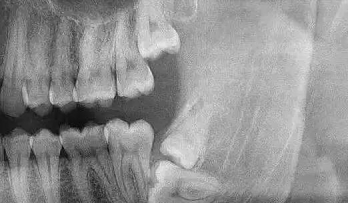

阻生牙(impacted teeth)是指部分萌出或完全不能萌出,且以后也不会自行萌出的牙。好发部位为下颌第三磨牙、上颌第三磨牙及上颌尖牙,其中阻生第三磨牙也叫做阻生智齿。

1、反复发作的冠周炎:智齿牙冠周围软组织与牙齿之间形成一盲袋,引起食物、细菌的积存,抵抗力下降时,出现冠周炎症发生。常表现为冠周组织红肿疼痛,以致影响咀嚼,吞咽,还常伴有张口困难及发烧,巴结肿大等全身症状。若炎症未及时控制,还可向颌周、颈部扩散,形成组织间感染、颌骨骨髓炎,甚至还可发生败血症、心包炎等严重全身并发症。

2、龋齿:阻生的智齿与第二磨牙之间容易积存食物残渣,而且不易清洁,很容易形成智齿和第二磨牙的龋齿而发生疼痛。